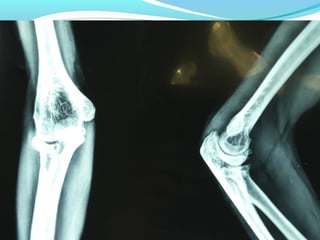

X-RAY